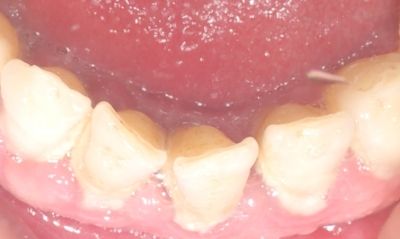

Autor zdjęcia/źródło: Rycina. Złogi naddziąsłowego kamienia nazębnego i zapalenie dziąseł (fot. W. Bereziewicz)

Pierwsze ogniska wapnienia w związku z obecnością soli mineralnych w ślinie pojawiają się w płytkach już po 6 godzinach, następnie zlewają się w blaszki i widoczne są w jamie ustnej zwykle po 3 dniach, wtedy powstaje kamień nazębny (ryc.). W skład kamienia nazębnego wchodzą: 70% sole nieorganiczne oraz 30% drobnoustroje i substancje organiczne.2

Wyróżnia się kamień nazębny: naddziąsłowy, który tworzy się powyżej brzegu dziąsła, oraz kamień poddziąsłowy, który powstaje w kieszonkach dziąsłowych.2 Złogi nazębne działają drażniąco na struktury przyzębia i przyczyniają się do rozwoju chorób przyzębia.